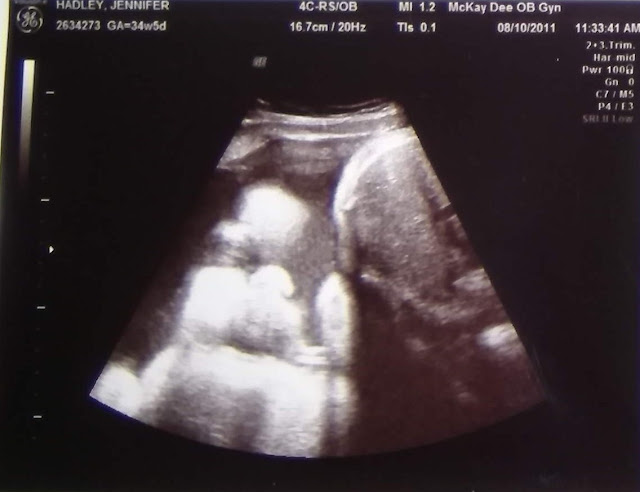

I only have a picture of Baby "B" from this appointment. It's a straight shot of her cute face. She has chubby cheeks! You can also see one eye, her button nose and lips.